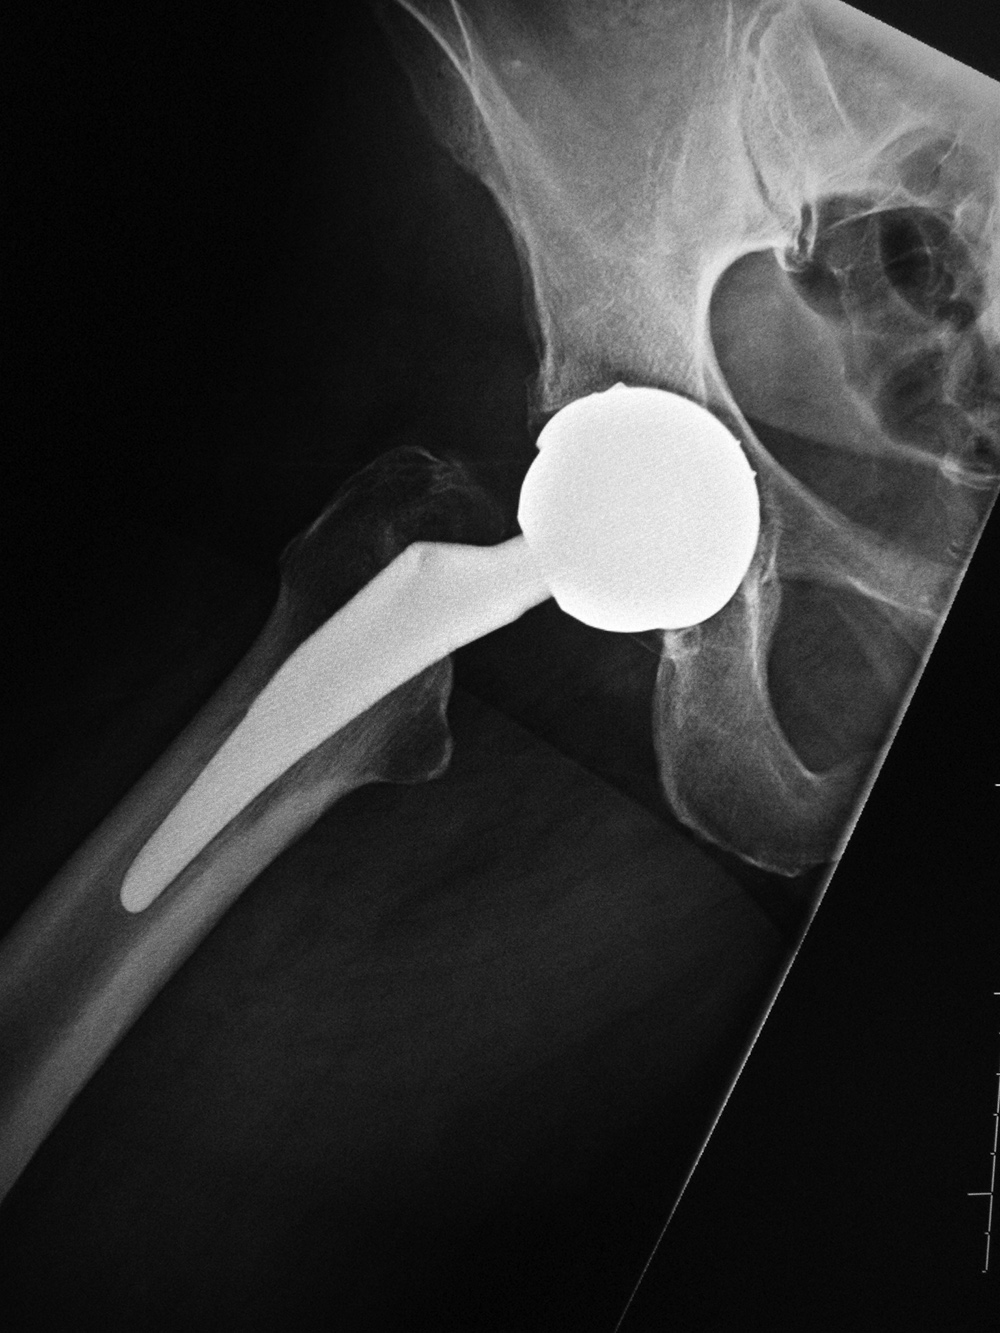

| Bipolar hemiarthroplasty (prosthesis) |

Bipolar hemiarthroplasty (prosthesis) |

Bipolar hemiarthroplasty (prosthesis)

| A free riding acetabular cup is press fit into the native acetabulum. The acetabular cup articulates with a prosthetic femoral head and stem component. From Benjamin, 1994 |

From Benjamin, 1994 |

92 year-old woman treated for left femoral neck fracture. From Taljanovic, 2005 |